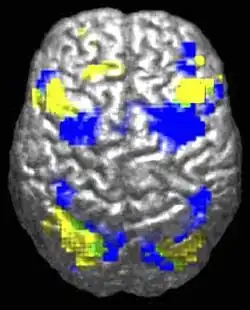

A human brain viewed from above. About 10% is highlighted in yellow and 10% in blue. There is a tiny green region (~0.5%) where they overlap.

Autistic individuals tend to use different brain areas (yellow) for a movement task compared to a control group (blue).[30]

The underconnectivity theory of autism posits that autistic people tend to have fewer high-level neural connections and less global synchronization, along with an excess of low-level processes.[31] Functional connectivity studies have found both hypo- and hyperconnectivity in brains of autistic people.[32] Hypoconnectivity is commonly observed for interhemispheric (e.g. lower neuron density in corpus callosum)[33] and cortico-cortical functional connectivity.[34] Some studies have found local overconnectivity in the cerebral cortex and weak functional connections between the frontal lobe and the rest of the cortex.[35] Abnormal default mode network (task-negative) connectivity is often observed. Toggling between task-negative network activation and task-positive network activation (consisting of the dorsal attention network and salience network) may be less efficient, possibly reflecting a disturbance of self-referential thought.[36] Such patterns of low function and aberrant activation in the brain may depend on whether the brain is performing social or nonsocial tasks.[37]